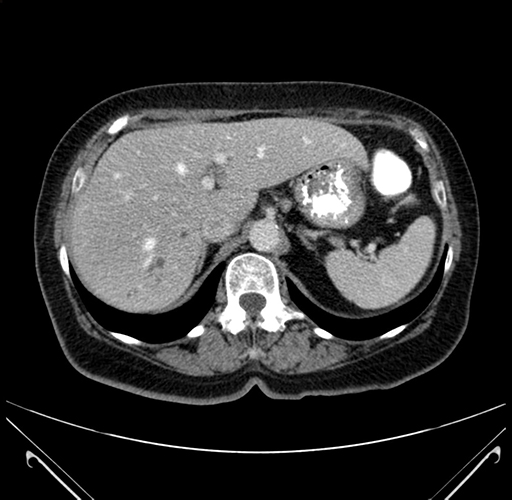

Pre-Chemo: Axial Venous

Axial Venous